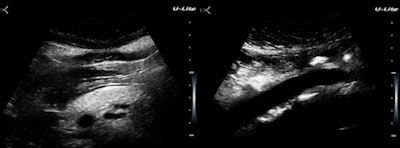

This is a strength of radiology and one that we share uniquely with pathology. This particular example was easy, because the diagnosis is just a descriptive term, but we're not always as lucky. The clinic population has a high prevalence of cholelithiasis, obesity, hypertension, and metabolic syndrome (figure 3).

There are two reasons why I am using up limited image real estate here with something as pedestrian seeming as a fatty pancreas. The diagnostic issue is not identifying obesity but in assessing cardiac and insulin resistance risks. Like fatty liver, pancreatic fat is a visceral fat deposition a big step closer to metabolic syndrome. The second is that the U-Lite does a much better job in the presence of obesity than I would have anticipated. Maybe this has to do with the submillimeter range gating?